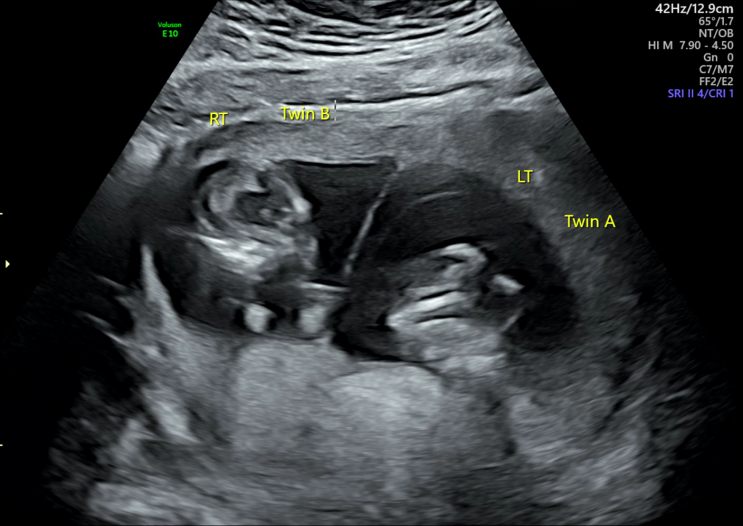

[임신일기]22주 4일차 입체초음파를 보다

3주만에 정기외래검진을 가는 날. 별다른 이유도 없고 단순 검진이라 그냥 아무 생각없이 갔는데, 입체초음...